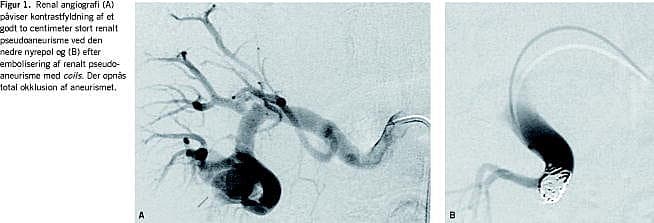

En 64-årig mand blev indlagt på grund af svær, behandlingskrævende arteriel hypertension og aftagende nyrefunktion. Isotoprenografi viste ikke tegn på afløbshindring, men gav mistanke om obstruktion af højre nyrearterie. Højresidig renal angiografi viste ingen nyrearteriestenose, men et to centimeter stort aneurisme i nedre nyrepol. Pseudoaneurismet blev superselektivt emboliseret med coils, hvorefter aneurismet var totalt okkluderet (Figur 1 ). Denne behandling påvirkede ikke patientens nyrefunktion.